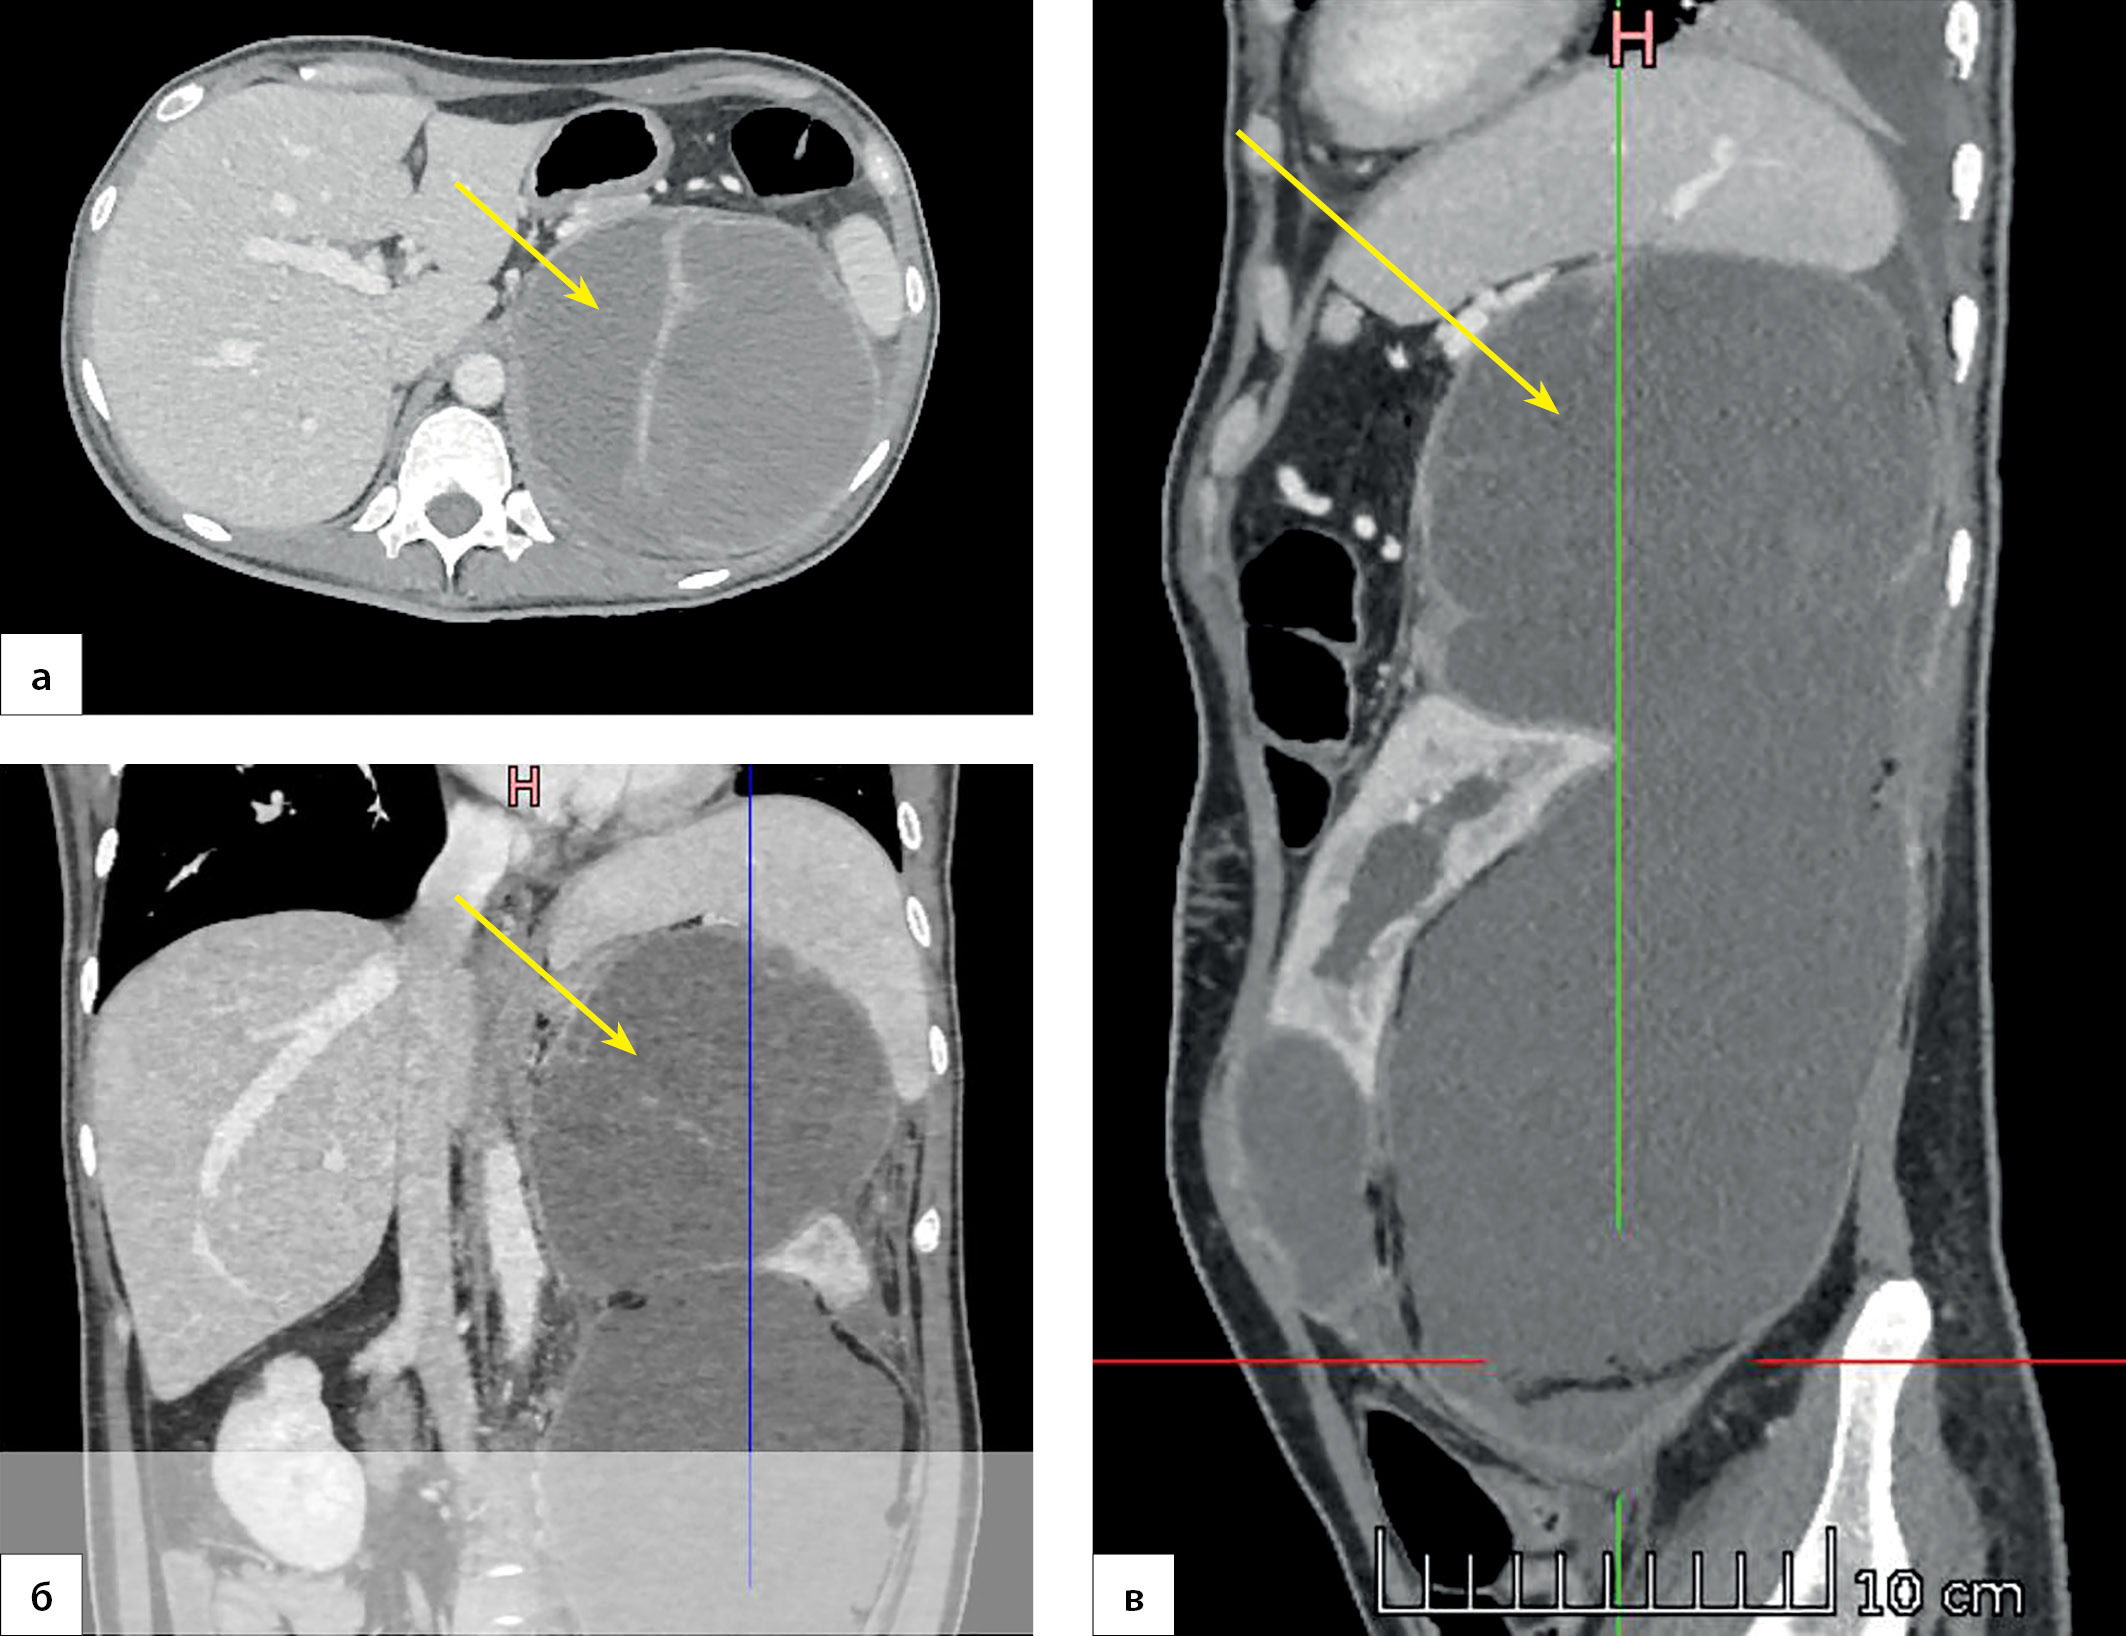

1. Рисунок 1. Пациентка П., 38 лет. МСКТ органов брюшной полости 31.05.2022 г. (венозная фаза), многоузловое образование слева (маркирована стрелкой), смещающее селезенку и сдавливающее левую почку: а) корональная проекция; б) аксиальная проекция; в) сагиттальная проекция. | |